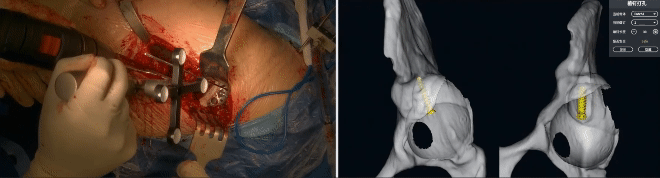

术式:基于镜像重建理念的VTS导航辅助左侧(DDH Crowe IV)全髋关节置换术

性别:女 身高:1.49m 体重:47kg。

诊断:左髋关节发育不良(Crowe IV型)

VTS系统辅助磨削

VTS辅助假体植入

VTS辅助植钉打孔